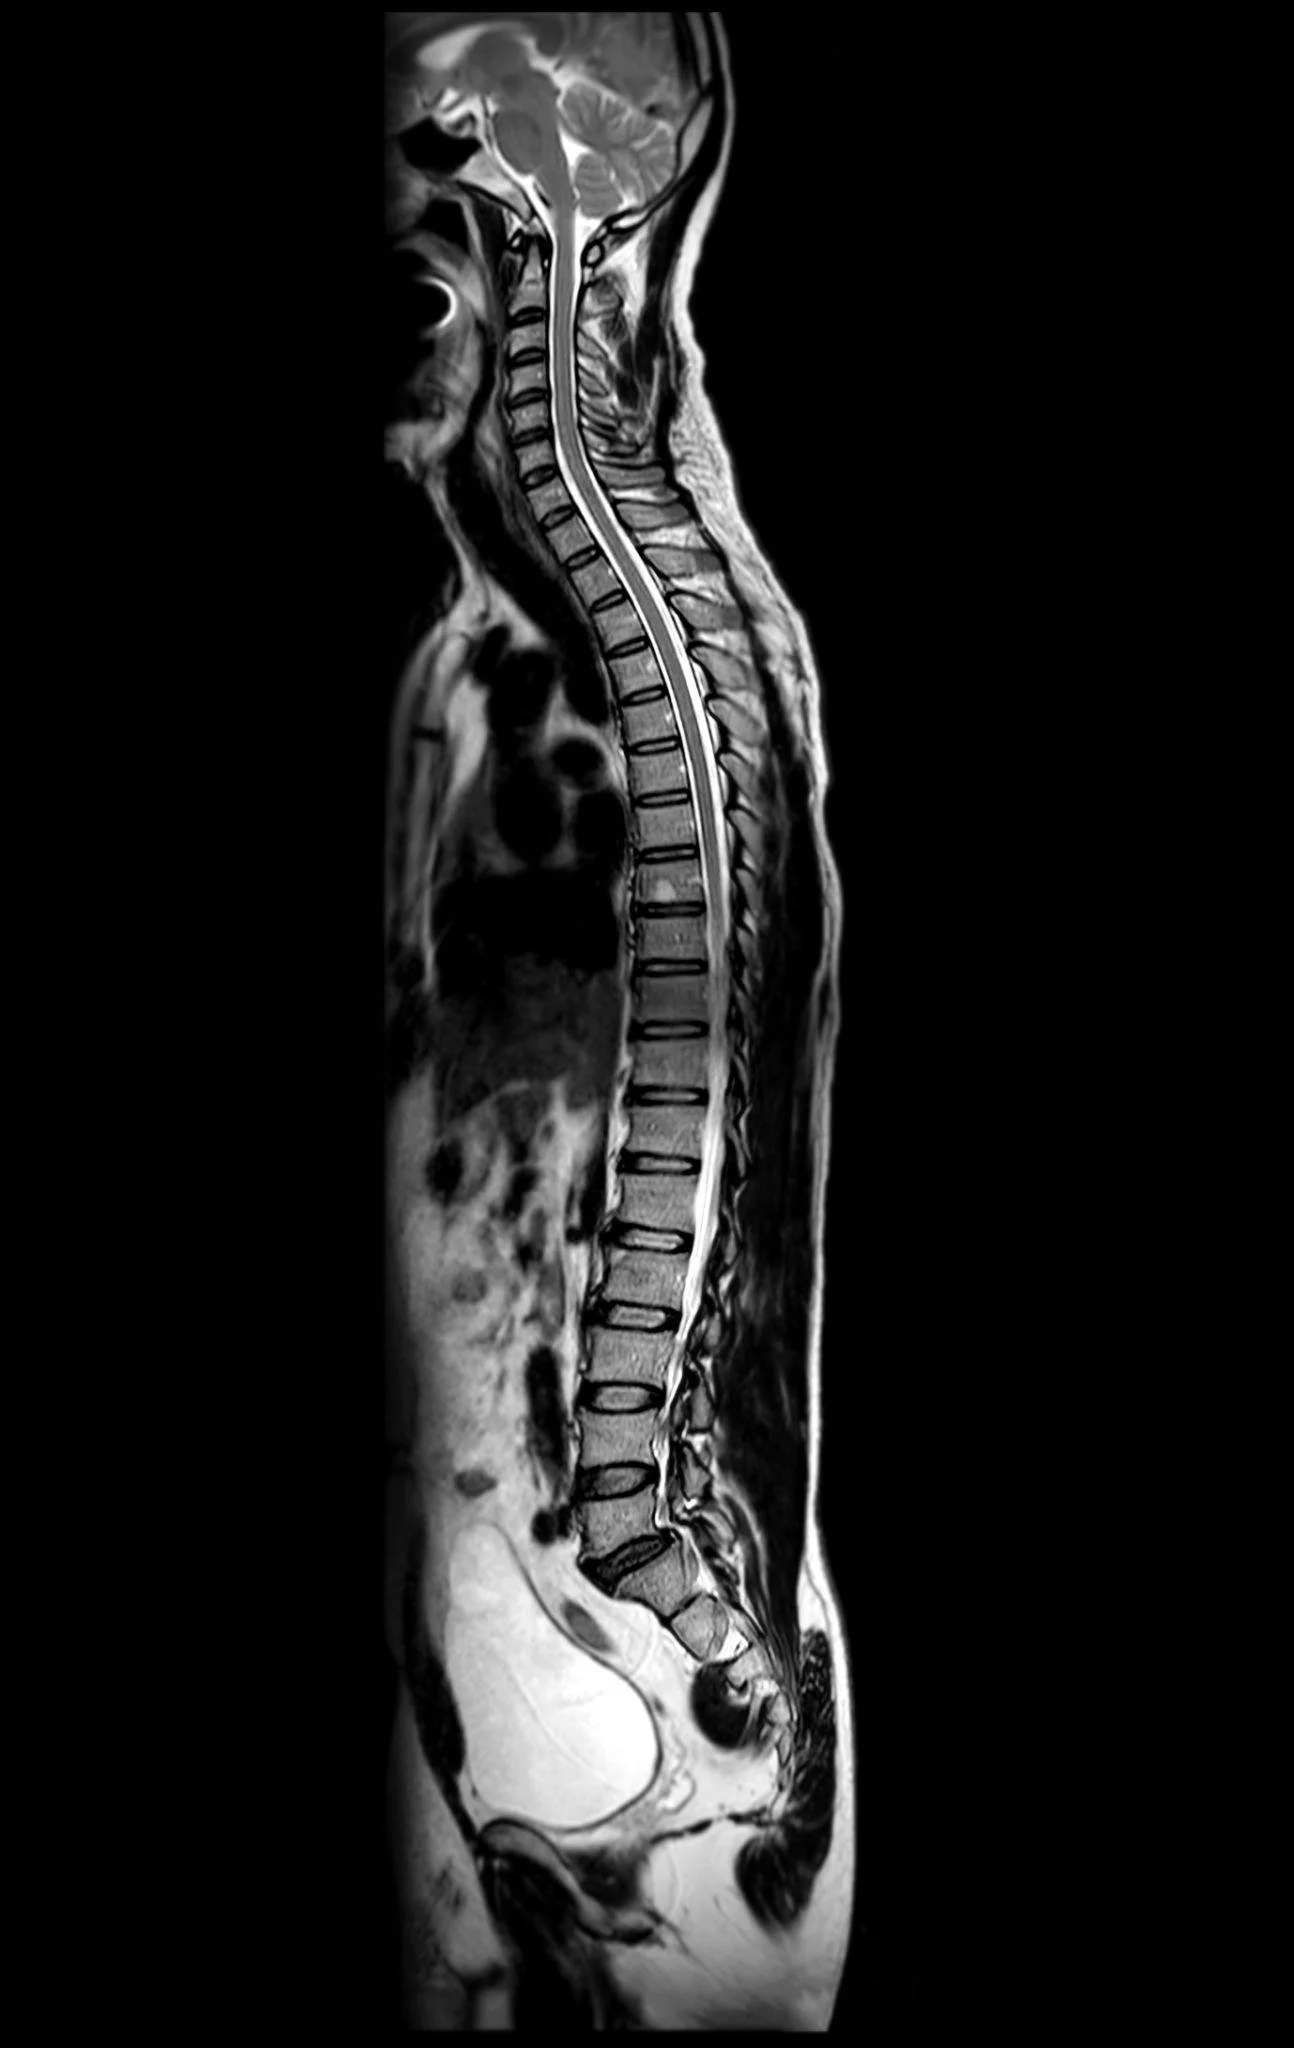

2D MRI of spine

Traditional 2D imaging remains highly precise and indispensable for diagnostics, but it places a significant cognitive burden on clinicians. Understanding complex anatomy from stacked image slices requires experience, spatial reasoning, and time.

In challenging cases, clinicians must mentally assemble multiple views to interpret:

• The depth and positioning of structures

• The relationship between organs, vessels, and pathology

• The spatial impact of tumors, lesions, or abnormalities

• The procedural approach required for treatment

While experts are skilled at this process, it can still slow interpretation, complicate interdisciplinary discussions, and make it harder to communicate findings clearly to patients and non-specialists.

Despite these advances, traditional 2D imaging modalities remain foundational to medical diagnostics. CT, MRI, and other imaging techniques provide the detailed data necessary to generate accurate clinical interpretations.

2D MRI image review

Interactive 3D visualization should be viewed as a complementary layer that enhances, rather than replaces, these established modalities. By combining the precision of 2D imaging with the spatial clarity of 3D models, clinicians gain a more complete and intuitive understanding of patient anatomy and pathology.

This integrated approach allows healthcare providers to leverage the strengths of both methods: detailed imaging data and immersive spatial insight.